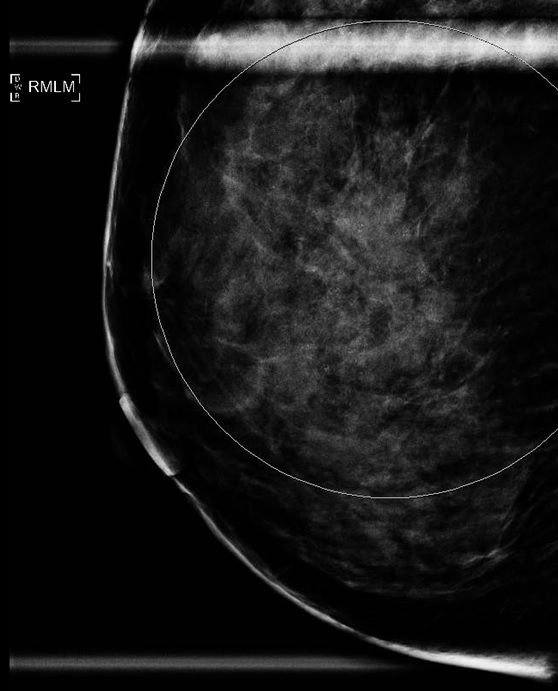

الحالة الثانية: اتضح وجود كتلة كبيرة في الصدر الأيمن بعد الفحص وعمل خزعة تحت الأشعة التلفزيونية ثم رنين مغناطيسي للصدر يوضح انتشارها. تم علاج المريضة وعمل رنين مغناطيسي يوضح صغر الكتلة بشكل كبير جدا ثم تم استئصال الثدي الأيسر بشكل كامل وترميمه جراحيا.